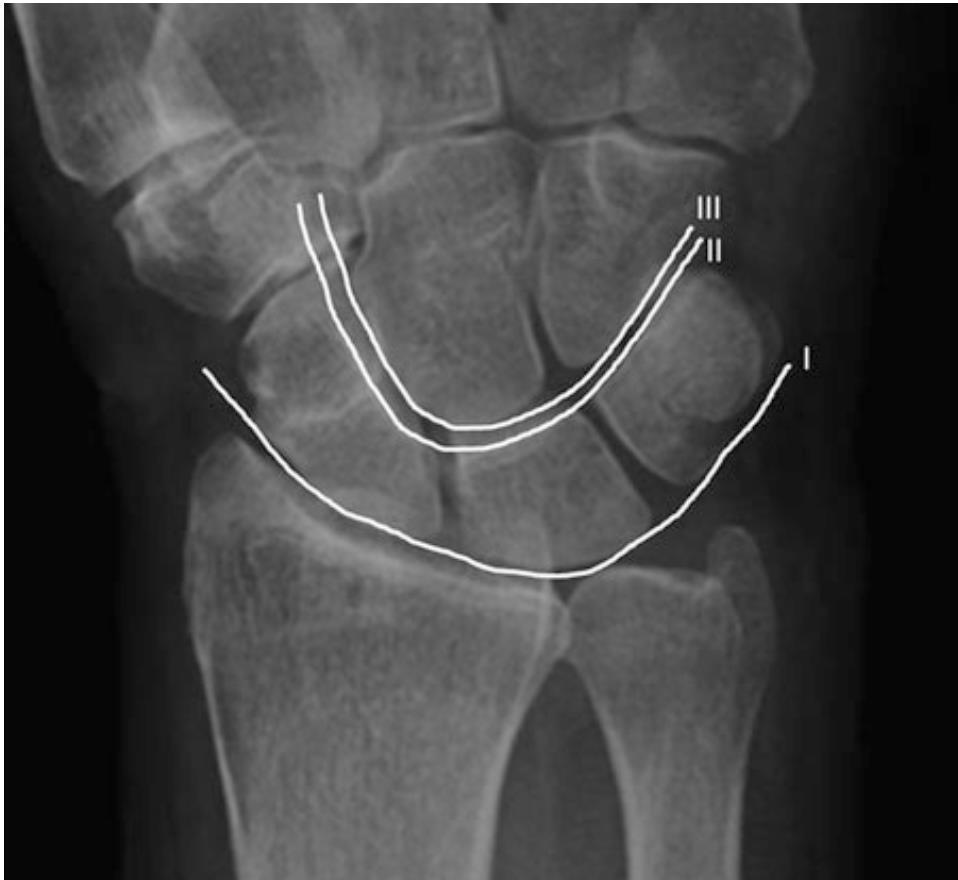

15. Anatomía radiológica del carpo

Marcela Pérez Muñoz, Camilo González Gómez…………….…………………………..